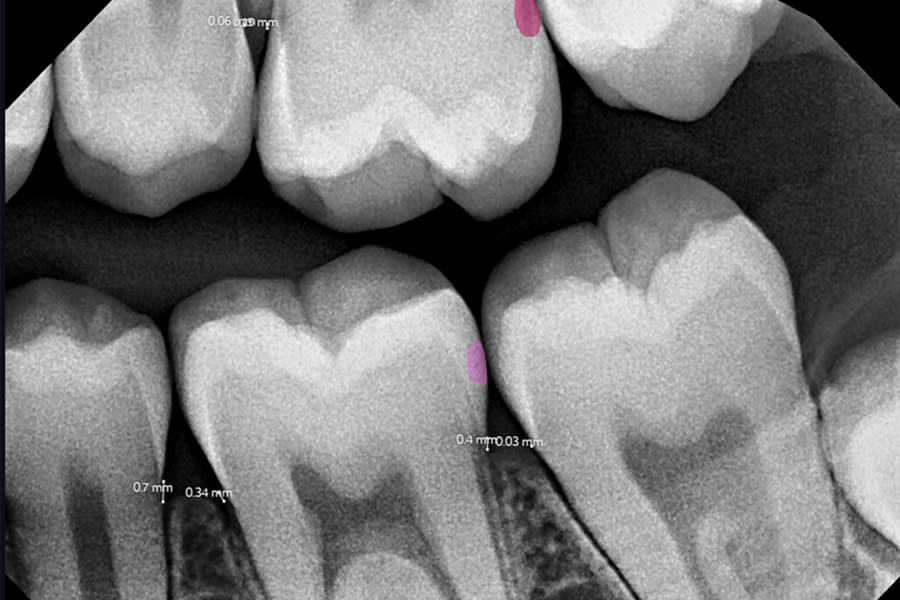

Case 2: Liam (Adolescent Patient, AI-Detected Lesions)

Liam, a 13-year-old male patient, had a lax diet typical of many adolescents, limited flossing, and only moderate home care. Despite nutritional counseling and home care instruction, AI-assisted imaging revealed incipient lesions on the distal aspect of tooth No. 14 (with No. 15 erupting) and the distal of tooth No. 19.

After cleaning, etching, and drying was performed, Curodont was applied, followed by application of fluoride varnish and adjunctive use of fluoride mouthwashes. AI-assisted imaging was used at baseline and at follow-up, supporting early detection and clear patient communication.

At follow-up visits, lesions were no longer detectable with AI or radiographically. Both patient and parent appreciated avoiding operative care, particularly given the challenges of isolating tooth No. 14 during eruption of No. 15. This case demonstrates the synergy of AI diagnostics with non-invasive therapy, shifting treatment from “watch and wait” to proactive repair. (Figure 3 and Figure 4)